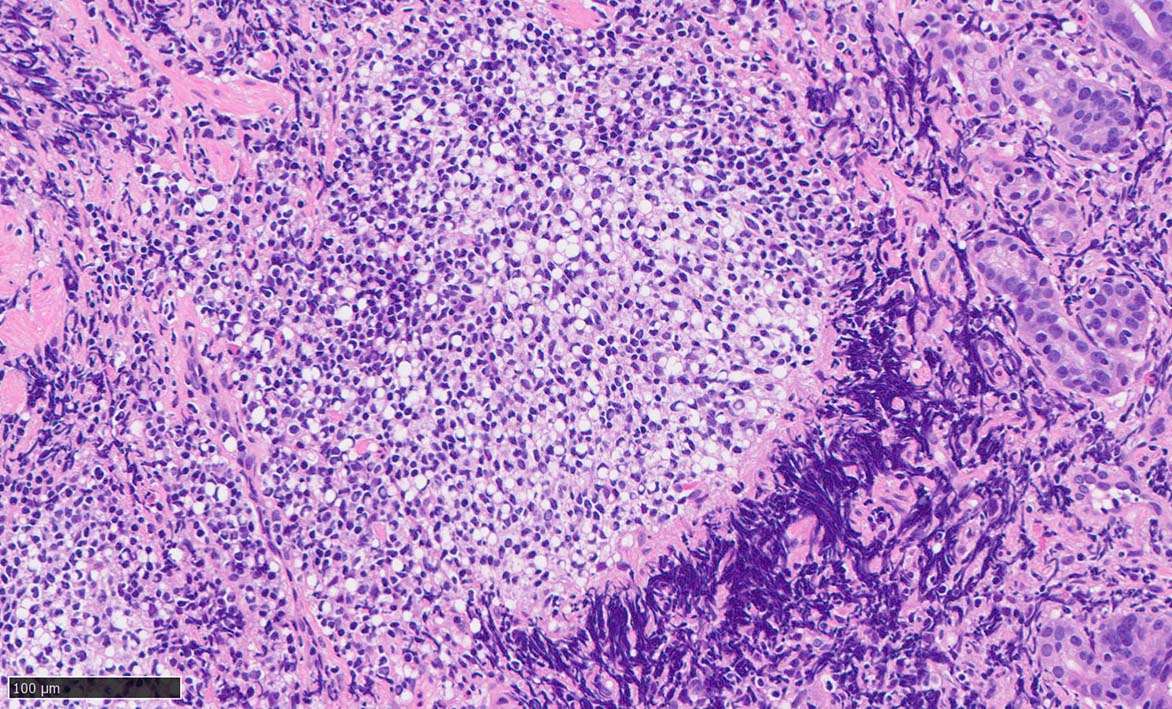

Signet-ring cell lymphoma of the stomach

60 year-old male. 胃生検組織

stomach biopsy, HE

x200